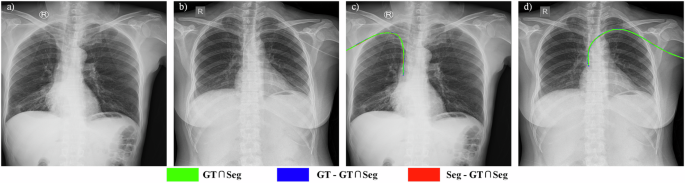

Figure 9 displays representative left- and right-insertion PICC radiographs along with their corresponding segmentation results. Green indicates correctly identified PICC segments, blue suggests missed regions, and red denotes erroneous detections. Both adult cases display predominantly green trajectories, indicating accurate catheter tracing along the entire PICC course with minimal discontinuities.

Despite its strengths, the proposed method exhibits certain limitations. The model remains susceptible to misidentification and under-segmentation when processing PICC radiographs with significant artifacts, particularly those containing other catheters or exhibiting suboptimal image quality. For example, Fig. 10a, b display original pediatric PICC radiographs, while (c) and (d) present their corresponding segmentation results from TopNet. In (c), a non-PICC catheter located in the upper-right region is erroneously identified due to its similar intensity profile. (d) illustrates a case of under-segmentation. Typically, catheters segmented by TopNet are correctly located within the right atrium adjacent to the thoracic vertebrae. However, in this instance, the greater distance between the right atrium and vertebrae caused the model to fail in segmenting the intrathoracic portion of the catheter, leading to suboptimal performance. Future work will focus on mitigating these issues by increasing the diversity of pediatric cases in the training dataset.